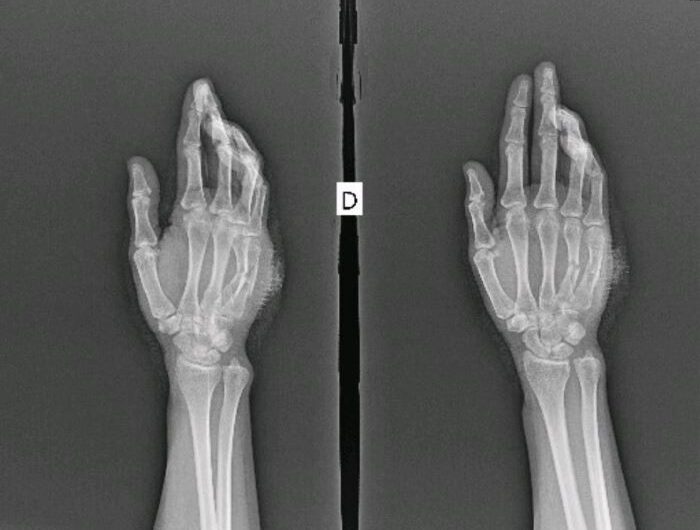

O crime ocorreu no fim do ano passado. A funcionária é lotada no Instituto Municipal de Trânsito. De acordo com as investigações, ela estava em casa na noite de 21 de dezembro de 2025 quando o ex-companheiro, cabo da Polícia Militar, invadiu o imóvel. Segundo o relato, o policial colocou a arma na boca da vítima e fez ameaças. Ela decidiu reagir e conseguiu afastar a arma, mas um disparo foi efetuado e atingiu uma das mãos. A vítima foi socorrida no Hospital de Emergência de Oiapoque e liberada depois de alguns dias após procedimentos médicos.

O cabo da PM, que não teve o nome divulgado na época, foi preso em flagrante. A prisão foi convertida em preventiva e ele continua detido. Abalada, a vítima foi para outro estado e precisará passar por 60 sessões de fisioterapia antes de uma cirurgia. Ela também passa por tratamento psicológico. O crime ocorreu quando ela estava finalizando o estágio probatório de dois anos, exigido para funcionários concursados.

A vítima terá que passar por 60 sessões de fisioterapia antes de uma cirurgia